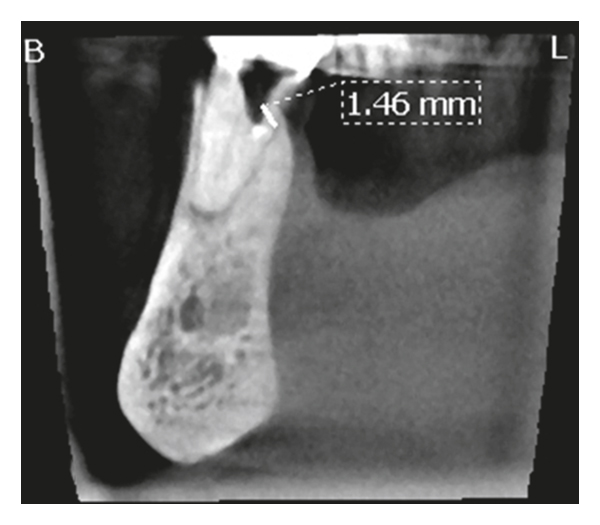

After anesthesia with 4% septocaine with 1 : 100,000 adrenaline (Ubistesin Forte, 3M ESPE, Seefeld, Germany) and rubber dam isolation (Hygenic Dental Dam, Coltene Whaledent, Langenau, Germany), an access cavity through the crown was prepared. The pulp chamber was presented with calcification, and no canal orifice could be identified under magnification. Ultrasonic preparing was performed at the depth of the preparation in an attempt to locate the canal orifice, but it was not successful. Following that, a 0.5 mm in diameter GP point was placed and compacted at the depth of the preparation where the canal orifice was estimated to be (Figure 1(b)). A cotton pellet moistened with sodium hypochlorite was placed in the access cavity, and the tooth was temporarily sealed with 4 mm of Cavit G (3M ESPE, Seefeld, Germany). The patient was referred for limited FOV CBCT of the area of the tooth (Morita 3D Accuitomo 170, J. Morita MFG Corp., Irvine, CA, USA). The coronal view of the CBCT revealed that the canal orifice was located 1.46 mm buccally and coronally to the GP point (Figure 1(c)). At the second visit, temporary filling materials were removed and ultrasonic preparing was performed buccally to the GP point at the position indicated by the CBCT. A microopener No. 10/.04 (Dentsply Maillefer, Tulsa, OK, USA) was introduced into an opening located along the buccal wall, and the canal location was confirmed using an apex locator (Root ZX II, J. Morita MFG Corp., Irvine, CA, USA). Root canal preparation was carried out using an endodontic rotary instrumentation system (RaCe, FKG Dentaire SA, La Chaux-de-Fonds, Switzerland) up to a 40/.04 file. Sodium hypochlorite 2.5% was used for copious irrigation. The canal was filled with GP and epoxy sealer (AH Plus, Dentsply Maillefer, Tulsa, OK, USA) using vertical compaction. The access cavity along with the space created lingually with ultrasonic preparing was sealed with composite resin, and a postoperative radiograph was taken (Figure 1(d)). It was not possible to recruit the patient for a yearly recall due to her advanced age.